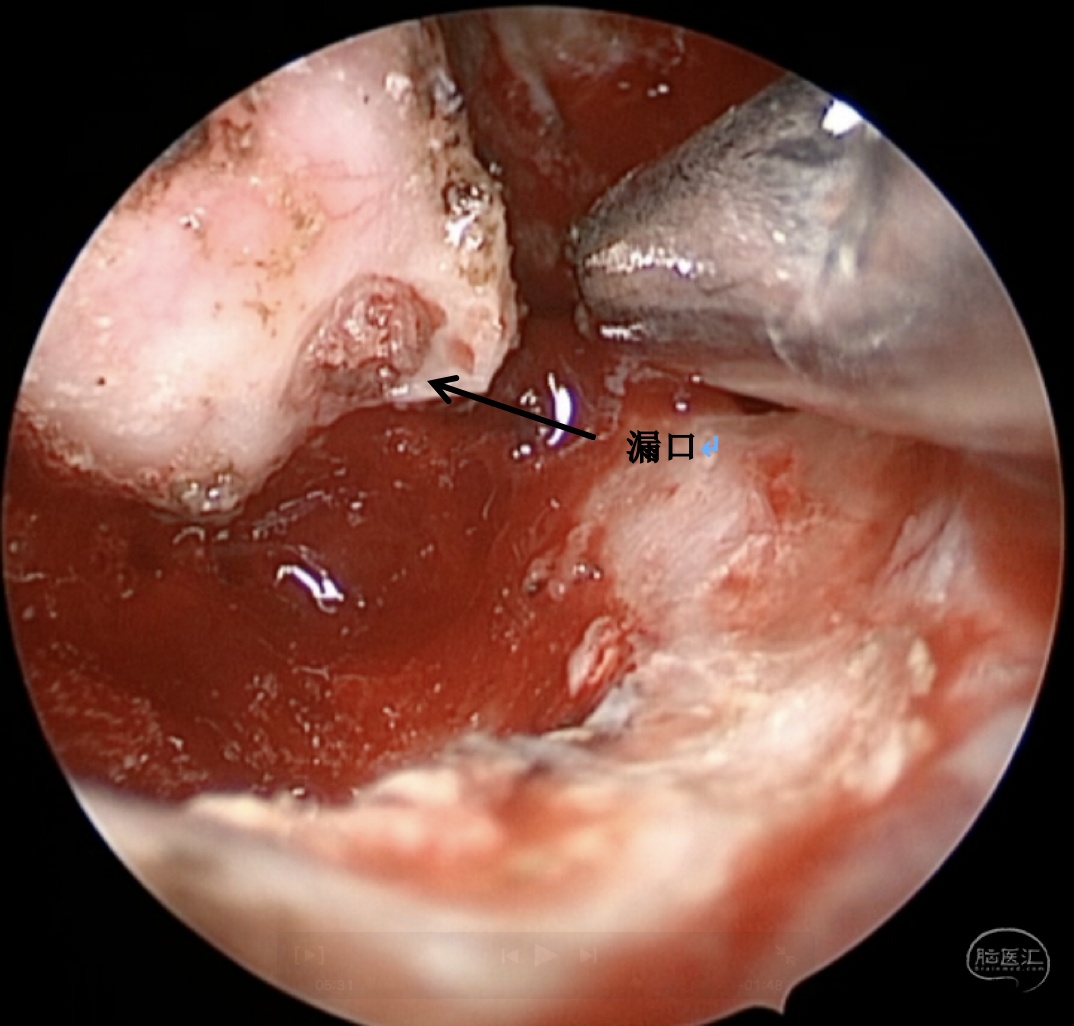

诊断:右侧蝶窦外侧隐窝脑膜脑膨出伴脑脊液漏。

病因分析:患者蝶窦过度气化,一直延伸至翼突,形成蝶窦外侧隐窝,造成中颅窝底出现薄弱区。患者第一次手术前因为松果体肿瘤,造成严重脑积水,颅内压明显增高,促使脑膜脑组织自颅底薄弱区疝出。但第一次手术术前并无脑脊液漏,而术后才出现脑脊液漏,可能的原因是:术前脑积水,造成颅内压较高,增高的颅内压一方面促使脑膜脑膨出,另一方面也迫使脑组织堵塞住了漏口,因而未出现脑脊液漏,手术后肿瘤全切除,脑积水缓解,颅内压下降,使得脑组织的堵塞漏口的作用下降,因此反而出现了脑脊液漏。

手术方案:内镜经鼻经翼突入路

术中情况: